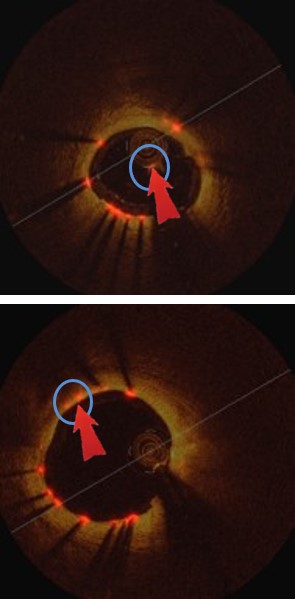

Refer to caption

(a) Image

(b) Labels

(c) F-RCNN

(d) Hong.

(e) Hyeong.

(f) Ours

Figure 4: Comparison of our detection results with existing comparison methods

Table 1 and Fig. 3(a) illustrate our method achieved the overall best performance when compared to the existing methods for strut detection. The traditional methods (Hyeong et al.[7], Hong et al.[5] and Ancong et al.[13]) using hand-crafted features with conventional classifiers achieved competitive performance when compared with Faster-RCNN method. Fig. 4(d) and Fig. 4(e) show two example results where both Hyeong et al and Hong et al methods fail to detect strut points where there is low-contrast to the background. In contrast, Faster-RCNN has the ability to combine deep semantic information and shallow appearance information in a hierarchical manner that enables it to encode image-wide location information and semantic characteristics. However, Faster-RCNN lacks constrain of the overall appearance of all the struts. Consequently, Faster-RCNN generates poor detection results for small struts (as shown in Fig. 4(c)).